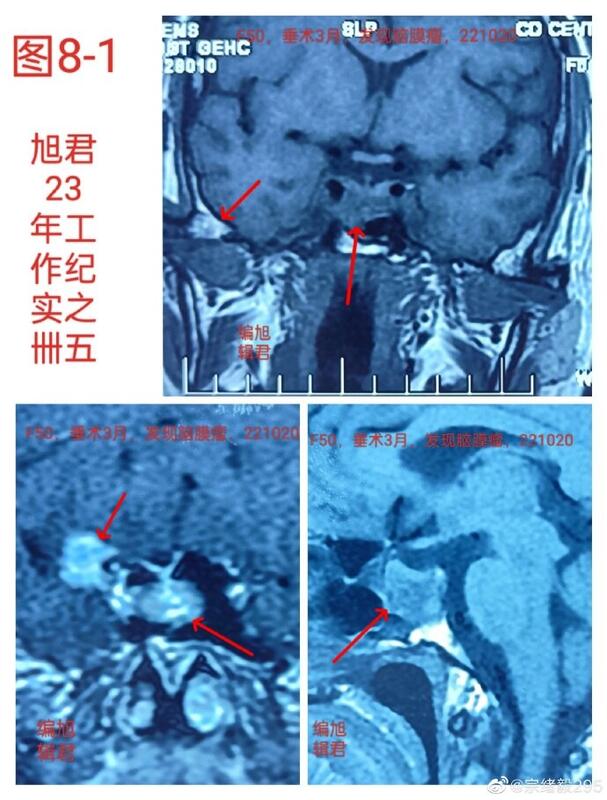

图8,1-2,某患者53岁,垂体瘤术后三年,术后三个月复查,发现右蝶骨嵴小脑膜瘤,复查无变化。

图8-1